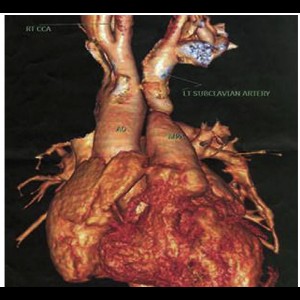

Cardio Thoracic Imaging

Isolated left brachiocephalic trunk arising from the main pulmonary artery with right aortic arch

Cardio Thoracic Imaging

Isolated left brachiocephalic trunk arising from the main pulmonary artery with right aortic arch